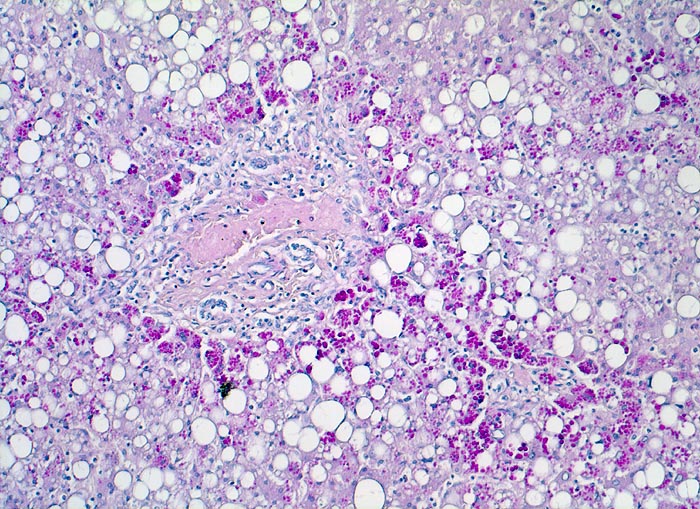

AP/ Leber bei alpha-1-Antitrypsinmangel

Leber bei alpha-1-Antitrypsinmangel